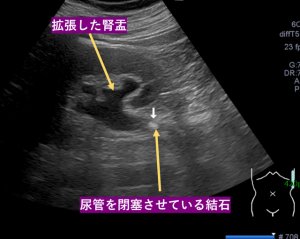

尿管結石|神戸市東灘区 摂津本山|いしむら腎泌尿器科クリニック。尿管結石・尿路結石の原因、症状、検査、治療について | 新橋消化器。レーザーによる尿路結石治療について | 泌尿器科 | 鎌ケ谷総合病院。尿管結石・尿路結石の原因、症状、検査、治療について | 新橋消化器。。長端13ミリ短端7.8ミリの巨大な尿管結石です非常に希で、希少な物になります激痛のなか排出したもので34歳男性の物になります!何かの研究にお役立てください